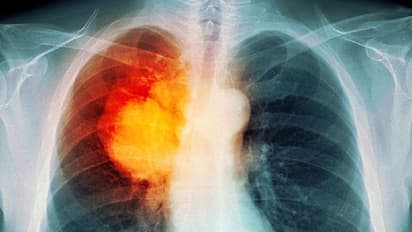

ലോകത്ത് തന്നെ വര്ധിച്ചുവരുന്ന രോഗങ്ങളുടെ പട്ടികയില് മുന്പന്തിയിലാണ് ശ്വാസകോശ അര്ബുദം അഥവാ 'ലംഗ് ക്യാന്സര്'. കണക്കുകള് പ്രകാരം 2018ല് മാത്രം പത്തര ലക്ഷത്തിലധികം പേരാണ് ശ്വാസകോശ അര്ബുദത്തെ തുടര്ന്ന് മരിച്ചതായി റിപ്പോര്ട്ടുകളിലുള്ളത്. ഇരുപത് ലക്ഷത്തിലധികം പേര്ക്ക് 'ലംഗ് ക്യാന്സര്' പിടിപെട്ടതായും റിപ്പോര്ട്ടുകള് സൂചിപ്പിക്കുന്നു.

ശ്വാസകോശ അര്ബുദം ബാധിക്കപ്പെട്ട് മരിക്കുന്നവരില് അധികം പേരുടെ കേസുകളിലും അവര്ക്ക് തിരിച്ചടിയായിരിക്കുന്നത് രോഗം കണ്ടെത്താന് വൈകി എന്നതായിരിക്കും. ഇക്കാര്യം ഡോക്ടര്മാര് തന്നെ സാക്ഷ്യപ്പെടുത്തുകയും ചെയ്യുന്നു.

എന്നാല് പലപ്പോഴും രോഗികള് ചികിത്സ തേടിയെത്തുന്ന സമയം വൈകുന്നതാണ് വലിയ പ്രതിസന്ധിയാകുന്നത്. ശ്വാസകോശ അര്ബുദം മൂലമുള്ള മരണനിരക്ക് വര്ധിക്കുന്നതിന്റെ ഏക കാരണവും രോഗം കണ്ടെത്താന് വൈകുന്നു എന്നത് തന്നെയാണ്.